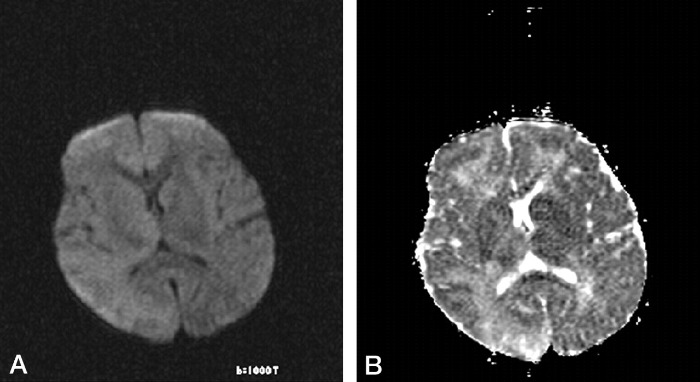

(B) ADC карта: повышение интенсивности и повышение значений ADC от пораженных областей (при измерении: 1,17, 1,18, 1,24, 1,49, 1,27, и 1,21 × 10−3 мм²/с).

Излюбленная локализация изменений: перивентрикулярное и субкортикальное белое вещество; базальные ядра, мозолистое тело, таламусы и спинной мозг поражаются реже. С прогрессированием процесса появляются признаки атрофии полушарий, мозжечка и продолговатого мозга, вплоть до тотальной потери белого вещества на терминальной стадии. Серое вещество вовлекается в сравнительно меньшей мере.